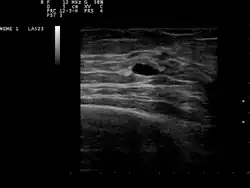

Ultrasound scan showing a small cyst in the breast

The cystic nature of a breast lump can be confirmed by ultrasound examination, aspiration[6] (removal of contents with needle), or mammogram. Ultrasound can also show if the cyst contains solid nodules, a sign that the lesion may be pre-cancerous or cancerous. Examination by a cytopathologist of the fluid aspirated from the cyst may also help with this diagnosis. In particular, it should be sent to a laboratory for testing if it is blood-stained.

Patients suspected of breast cysts will normally be given a diagnosing mammogram, although they are not suspected of cancer. This type of mammogram provides the doctor with the possibility of performing a breast ultrasound at the same time and this is the reason why they are often preferred over the screening mammograms. Breast ultrasound is considered the best option when diagnosing breast cysts because it is 95 to 100% accurate, it provides a clear image on the cyst's appearance (simple or complex) and it may also distinguish between solid lumps and fluid-filled cysts, which a mammogram cannot do.[7] Breast ultrasounds are performed with the help of a handheld medical instrument which is placed on the skin, after a special type of fluid has been applied on it. The instruments picks up the echo resulted from the sound waves it sends to the breast. These echoes are transmitted to a computer which translates it into a picture.